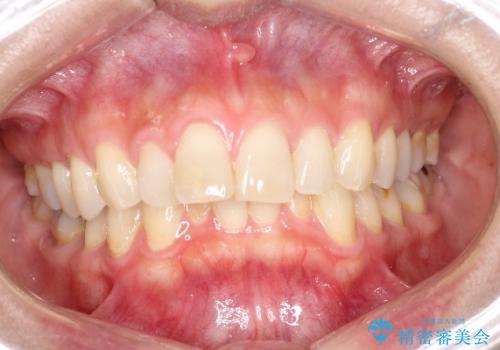

- 前歯の凸凹を主訴に来院されました。

臼歯部の遠心移動を行いながらスペースを作り、インビザラインにて前歯をきれいに並べることができました。

今回の治療計画では臼歯部の遠心移動とIPRを行っています。